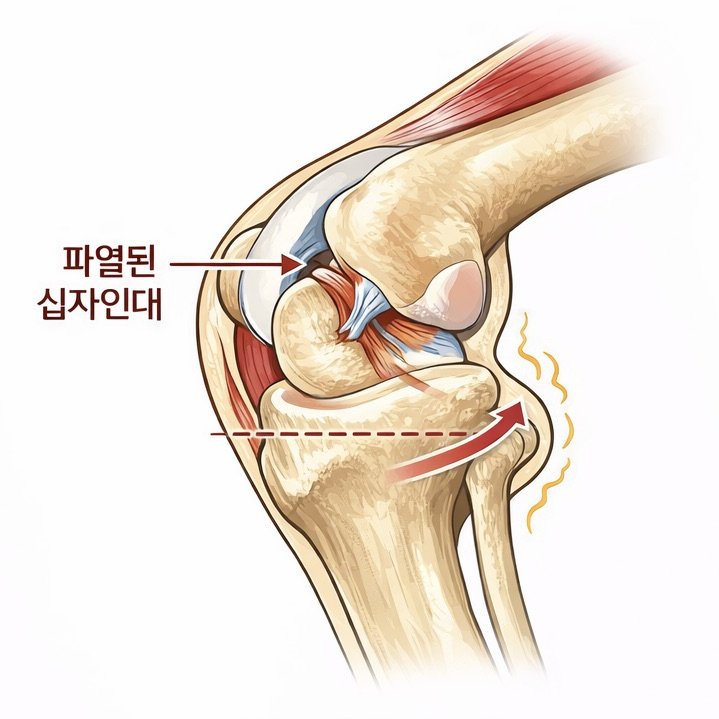

슬개골 탈구 수술은 단순히 빠진 뼈를 제자리로 돌려놓는 수술이 아닙니다.

무릎 관절의 정렬, 뼈의 구조, 연부조직 상태를 종합적으로 판단해 아이에게 맞는 수술 계획이 필요합니다.

슬개골 탈구 수술은 정확한 진단과 수술 환경이 결과를 좌우합니다.

수술 전·후 방사선 검사를 통해 관절 정렬과 수술 결과를 객관적으로 평가합니다.